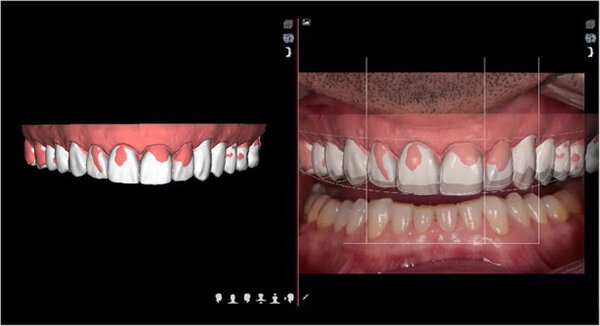

Se analizó el protocolo de documentación dinámica del DSD. Se grabará videos con un teléfono inteligente desde cuatro ángulos diferentes calculados para lograr una simetría facial armoniosa de la sonrisa: un video frontal de la cara sonriente con y sin el retractor de labios y mejillas, un video de perfil, un video de las 12 en punto y un video de la oclusión anterior perpendicular al nivel oclusal sin espejo.

Fig. 4. Protocolo DSD: imagen del paciente sonriendo con un retractor de labios y mejillas.

Se grabaron cuatro videos complementarios para el análisis funcional, estructural y facial: una consulta sobre las expectativas del paciente, un video fonético de 180 °, un video funcional intraoral y un video estructural intraoral con retractor de labios y mejillas (Fig. 5). La información fue transmitida al laboratorio DSD. El objetivo principal de la técnica DSD es combinar las fotografías de las tres vistas (oclusal, frontal y de las 12 en punto) con una regla digital para recrear las proporciones correctas de sonrisa mediante un análisis de video (marco de sonrisa).

El marco de sonrisa se creó de la siguiente manera, teniendo en cuenta la simetría facial: arco facial digital, forma y posición de la curva de la sonrisa, determinación del ancho utilizando la cantidad dental estética recurrente, proporciones de longitud del diente, curva papilar del margen gingival, arco de Cupido y curva mandibular. Las proporciones en 2D de la sonrisa se convirtieron con el software CAD en un modelo de simulación digital en 3D. El archivo 3D resultó en formato STL se transmitió a una impresora, que creó un modelo con el nuevo diseño. Después de identificar para producir una matriz hecha de bisacrilo (Estructura 3, VOCO) para la maqueta motivacional (Fig. 6).